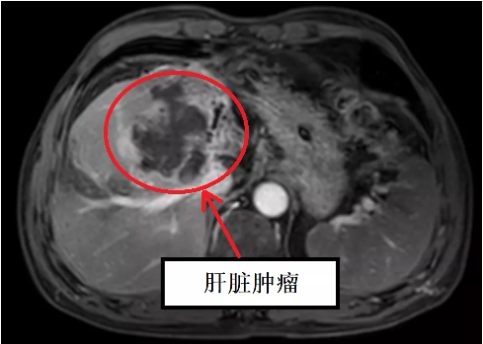

据肝胆·介入科徐耀端主任介绍,患者李某某,男性,56岁,石屏人,在3个多月前发现肝脏占位,其间,辗转云南省内多家三甲医院均被认为不能通过手术切除肝脏肿瘤及癌栓。而后,患者经过多方打听,于2021年11月16日到红河州第三人民医院肝胆·介入科就诊。患者入院后给予完善3.0 T核磁共振及320排CT等相关检查,经过该院肝胆·介入科、肿瘤内科、放射科、放疗科等9个科室专家参与的专病多学科会诊(MDT)讨论,研究制定详细手术方案,并于2021年11月23日在红河州第三人民医院肝胆·介入科行“左半肝切除+尾状叶切除+门静脉切开取栓术”,手术过程顺利,术后患者恢复情况良好,于2021年12月1日顺利康复出院。